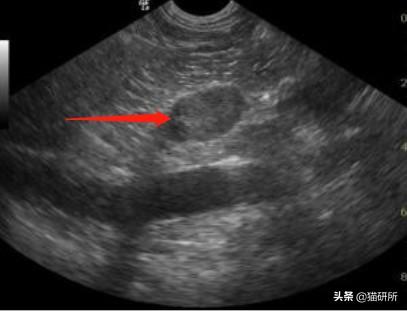

➤ 超声检查:发现腹腔内隐睾

(诊断敏感性强,尤其在睾丸发生肿瘤化或位于腹股沟时)

未出鞘的蛋蛋

阴囊脂肪和腹股沟淋巴结可能与隐睾混淆,腹部睾丸有的没有办法触诊或超声显示,需要开腹探查。图自@曾医生